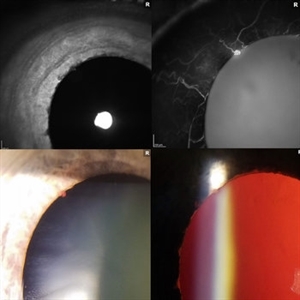

Choroidal Melanoma through the Pupil

External image of the left eye of a man with metastatic choroidal melanoma, secondary to lung cancer. There was an obstruction of view to the inferior retina, and this prompted the photographer to pull back to see what the problem was.

Photographer: Olivia Rainey

Imaging device: Topcon 50dx

Condition/keywords: choroidal metastasis, color photo, external photography